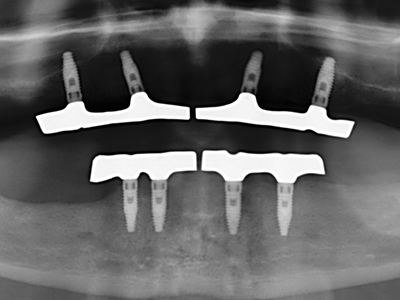

Abb. 13: Bei diesem 52-jährigen Patienten ist bei 4 mm UK-Restknochenbreite während des Bone Splittings auf eine ausreichende Wasserkühlung zu achten.

Abb. 14: Einbringung von vier konischen RSX-Implantaten (Bego Implant Systems, Bremen).

Abb. 15: Die röntgenologische Ein-Jahres-Kontrolle zeigt stabile Verhältnisse des Knochenniveaus.

Abb. 16: Auch intraoral stabile Verhältnisse mit Einbettung der Implantate in keratinisierter Gingiva.